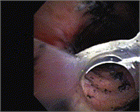

1. 気道損傷の診断に気管支ファイバースコープを施行することが勧められる(推奨度1)